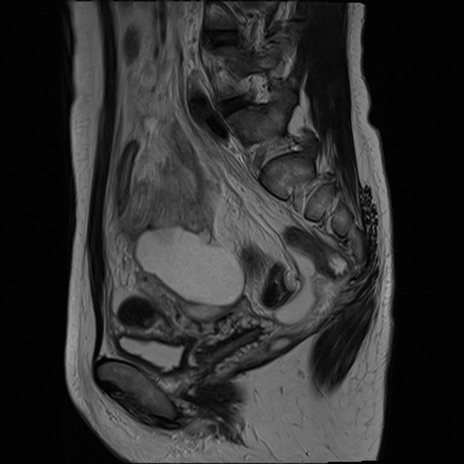

症例39 T2WI(矢状断像)

MRI(4日後)